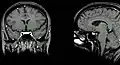

Гипофиз на сагиттальном и корональном срезах МРТ с контрастным усилением